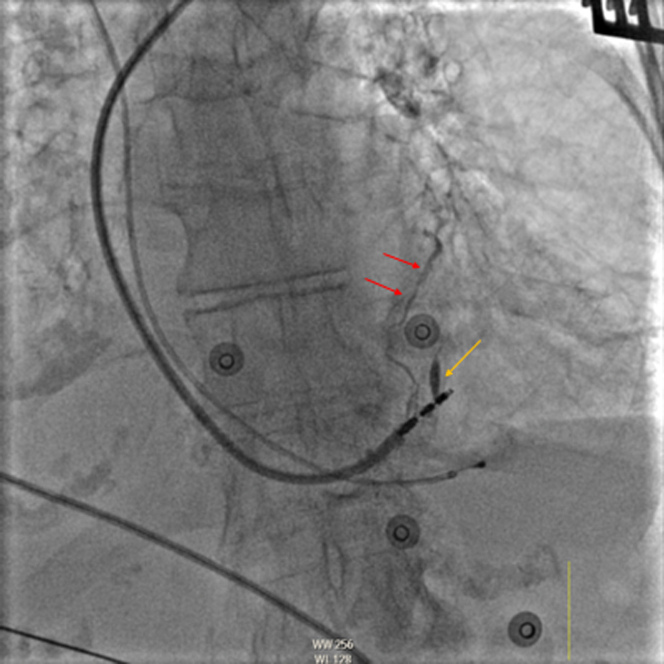

Figure 1.

Case 1: Fluoroscopy of a Stylet-Driven Left Bundle Branch Pacing Lead in the Left Anterior Oblique Projection

Contrast material filling a high anterolateral venous branch through the thebesian veins (red arrows) and tract created by the initial lead position (yellow arrow) is visible.

A decision was made to proceed with dual-chamber pacemaker implantation using conduction system pacing targeted by His or LBBAP, which is the preferred practice at our institution (Geisinger Heart Institute, Geisinger Commonwealth School of Medicine, Wilkes-Barre, Pennsylvania, USA). Infra-Hisian block was noted during the procedure, and a stylet-driven left bundle branch pacing (LBBP) lead was implanted. Nonselective left bundle branch pacing (NS LBBP) capture was obtained with a threshold of 0.9 V at 0.4 milliseconds and a stimulation to peak left ventricular activation time (pLVAT) of 60 milliseconds. Unipolar pacing impedance was 721 ohms. Approximately 2 mL of contrast material was injected through the sheath to gauge the depth of implantation. A small area of septal staining was noted next to the lead tip along with flow of contrast material through the coronary venous branches into the body of the CS (Figure 1, Video 1). No residual contrast material was noted on fluoroscopy after sheath removal. Follow-up TTE immediately post-procedure and 3 months after implantation showed an appropriate lead position without evidence of septal perforation or fistula formation. Electrical parameters remained stable on subsequent device checks.